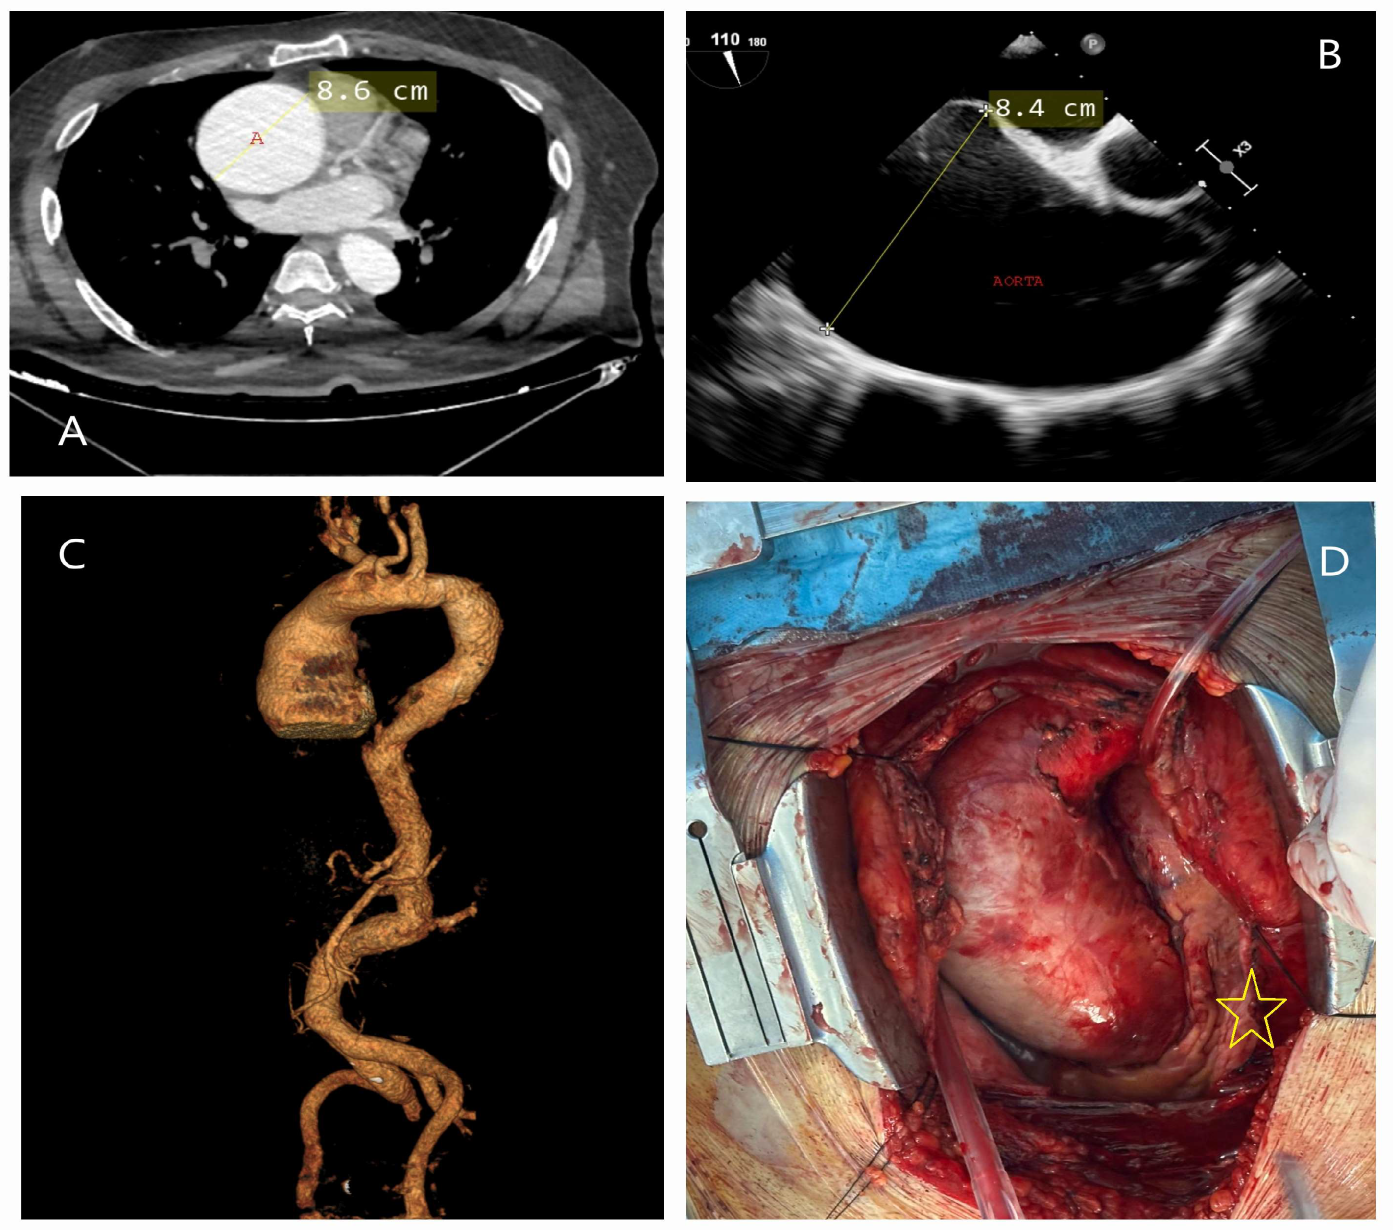

4.2. Genetic-Associated Aortic Syndromes

5.2.2. Echocardiography

5.2.3. Computed Tomography